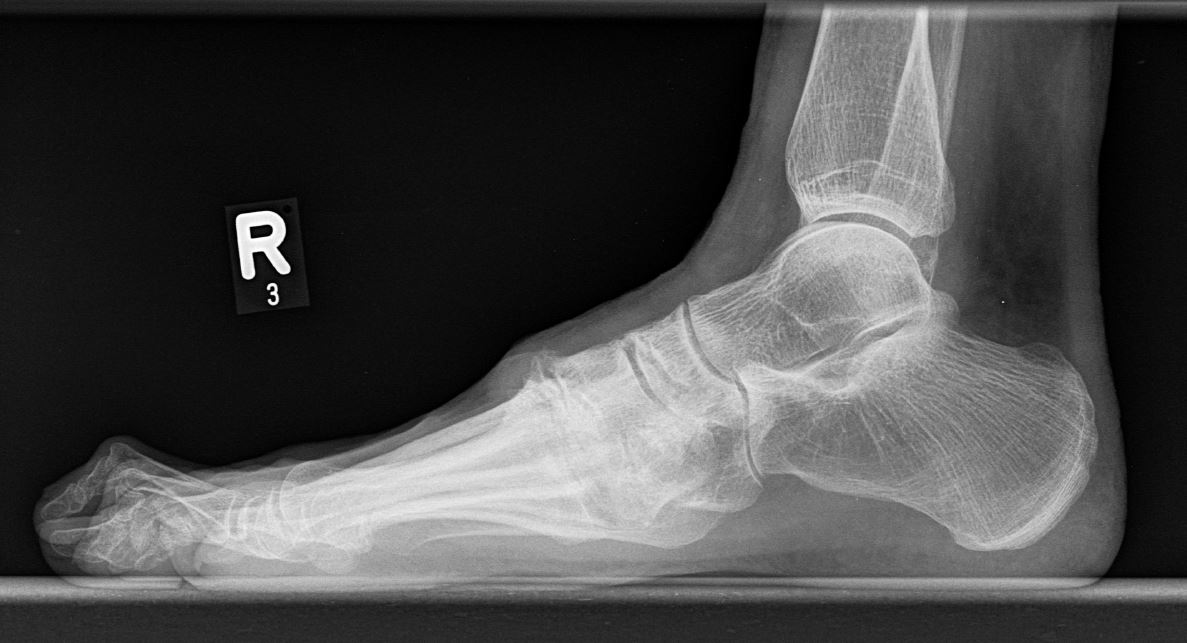

Eine Röntgenaufnahme unter Belastung mit Abbildungen des ganzen Fußes a. p. (mit 15-20° Röhrenkippung) und seitlich, sowie Schrägaufnahmen, reichen meist zur Diagnose. Manchmal ist ein MRT und DVT ergänzend hilfreich. Selten wird die Indikation für ein SPECT CT gestellt (Abb. 6).

• konventionelle Röntgenbilder mit Belastung im Stehen a. p. und seitlich, ggf. schräg (Abb. 9, 10 und 11).